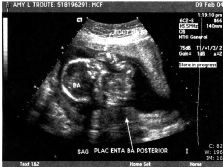

| We had our BIG ultrasound on February 9. Here are a few of the 111 pictures that were taken (everything from areas of the brain to little tiny kidneys) in our nearly 2-hour appointment (click the pictures to get a larger view – note the one where Baby A’s foot is right above Baby B’s head – so cute!!). The babies were moving so much that the tech had to literally hold them down with the ultrasound wand to get the detailed pictures she needed! Talk about uncomfortable!! Whew!! We were thrilled to hear that they’re developing perfectly – measuring in at 14cm and 9oz each!! They even bumped my due date up a week since the babies were measuring bigger than normal – music to our ears!! We’re still shooting for late June… I’d be at 36 weeks on my birthday – I’d love to share June 17 with the twins…or our anniversary June 23, or Father’s Day… ;o) We heard the heartbeats at a doctor’s appointment on 2/18 and my “theory” of their different heart rates signaling “boy and girl” was blown… In each of our past appointments there was a 10-15 beat difference between the two, but this time both were right at 160 beats per minute. I guess Reese is right – I really have no idea who’s in there! This week (2-16 to 2-20) I’ve started to really feel the babies moving! They’re especially active from 2-5 in the afternoon… makes it so hard to concentrate! I love it! I can't imagine how it's going to feel once they weigh more than 9 or 10oz each... Two 4 or 5lb kiddos in there packing on the pounds, rolling around and sticking their feet in each other's faces... Hahaha! What an image!! And the thought of them being most active at night... The adventure is only beginning!" |